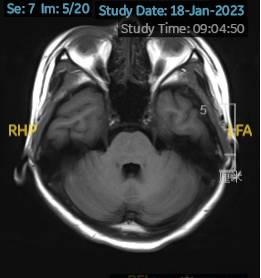

2023.01.18颅脑MR平扫示双侧基底节区及桥脑异常信号,考虑渗透性神经脱髓鞘综合征可能,见图1。

图1 2023.1.18颅脑MR成像示双侧基底节区及桥脑见对称性片样长T1长T2信号,FLAIR呈高信号。脑室、脑池、脑沟、脑裂未见明显异常。中线结构居中。小脑、脑干未见明显异常信号。